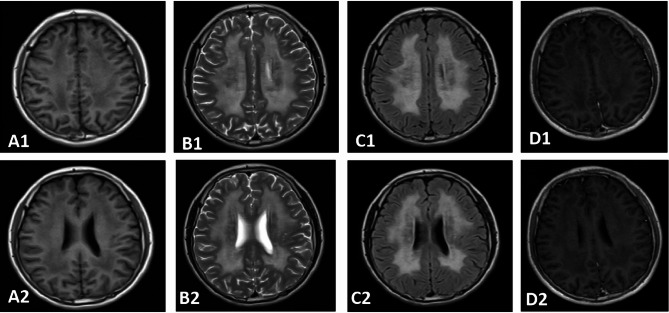

Results: The proband exhibited characteristic MNGIE features, including gastrointestinal dysmotility, diffuse leukoencephalopathy on brain MRI (magnetic resonance imaging), and electrophysiologically confirmed peripheral neuropathy. Muscle biopsy revealed ragged red fibers, cytochrome c oxidase-deficient fibers, and enhanced succinate dehydrogenase activity in blood vessels, consistent with mitochondrial dysfunction. Genetic analysis identified a novel TYMP variant (c.1268T > G, p.Leu423Arg) and a known variant (c.131G > C, p.Arg44Pro) in the proband, both classified as likely pathogenic according to ACMG guidelines. Molecular analysis of other 11 family members detected heterozygous carriers of either the c.1268T > G or c.131G > C variant in six asymptomatic individuals. In silico analysis confirmed that both variants are highly conserved and likely pathogenic. Protein modeling revealed that both variants compromise structural integrity and conformation, impairing TP function. Homozygous or compound heterozygous missense variants were identified as the predominant genetic alterations in 16 Chinese MNGIE cases, with gastrointestinal and neurological symptoms being the most common clinical manifestations.